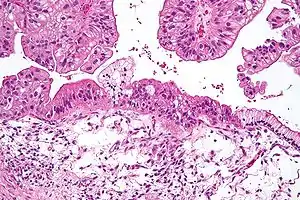

![]() Муцинозная опухоль яичника низкого потенциала злокачественности. Среднее увеличение, окраска гематоксилин-эозином. Муцинозная опухоль яичника низкого потенциала злокачественности. Среднее увеличение, окраска гематоксилин-эозином. | |